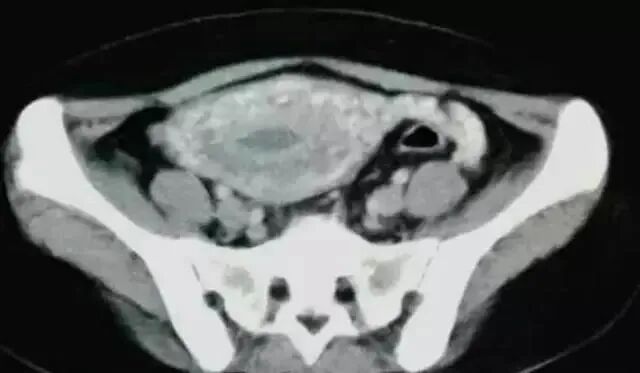

典型案例